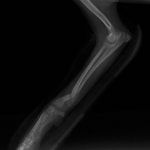

症例3:キルシュナーワイヤーのピンニングによる整復

ペルシャ猫 11ヶ月齢 雄

他院にて左大腿骨遠位の成長板骨折(salter-harrisⅠ型)が認められており、治療相談を目的として来院。当院にて、キルシュナーワイヤーを用いたピンニングにより骨折部位の整復を行いました。術後の経過は良好で、現在も経過観察中です。

術前レントゲン

術後レントゲン